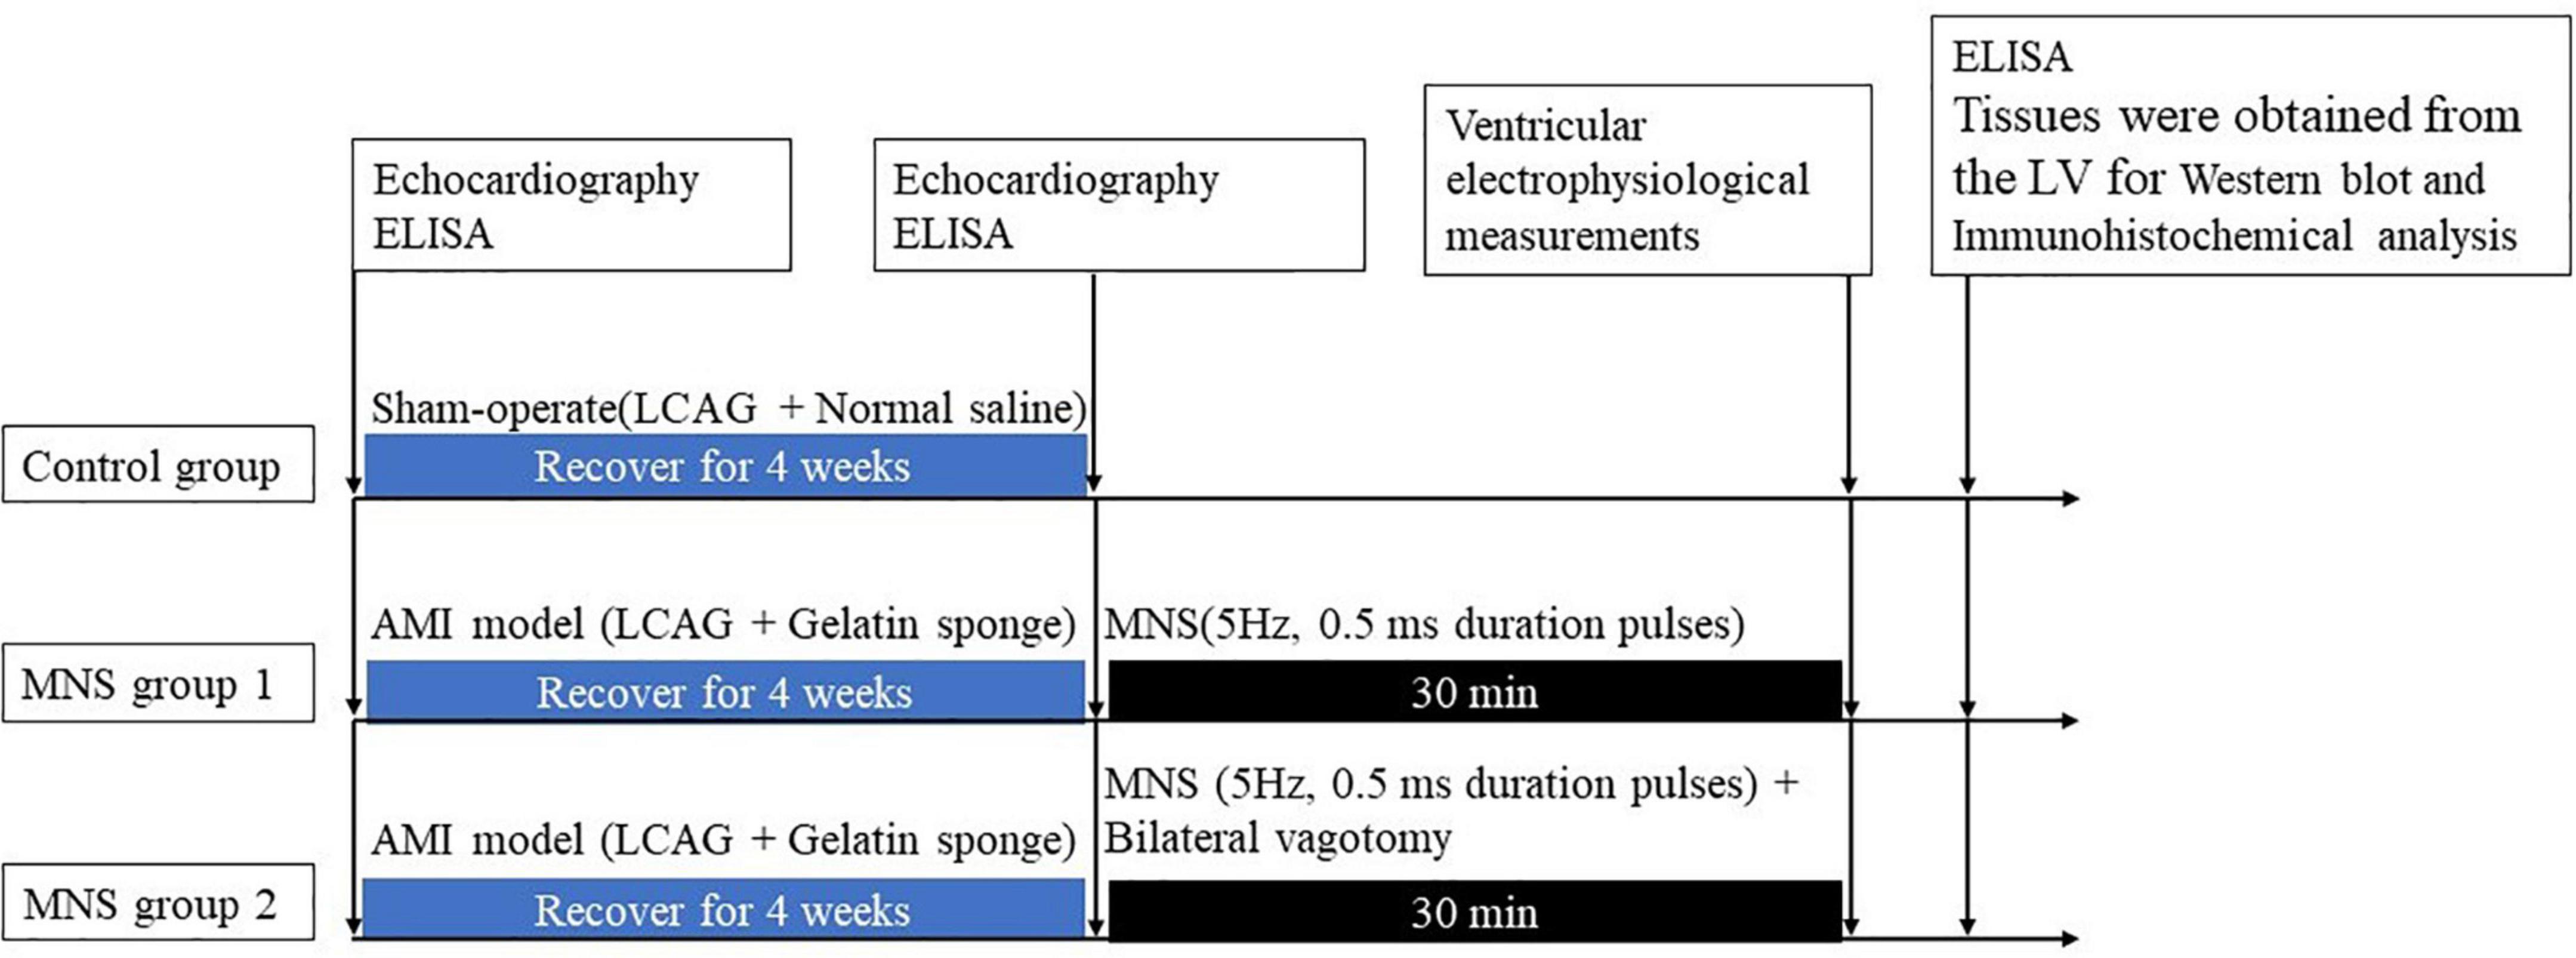

The MI model was established using catheter intervention. After administering stable anesthesia to all dogs, we injected 1000 U of heparin; then, we inserted hemostatic sheaths into their right femoral artery. Using X-ray fluoroscopy, a 5 F catheter was inserted into the left coronary artery to determine a coronary angiogram. Keeping the 5 F catheter positioned at the left anterior descending artery, a Radifocus SP catheter was delivered to the distal anterior descending artery through the 5 F catheter. A gelatin sponge with normal saline was injected into the distal anterior descending artery in 15 dogs. Notably, if the ST segment had no significant changes, the gelatin sponge with normal saline was reinjected. When the chest lead ST-segment was elevated, acute MI was achieved (Figure 1). The control group consisted of the other seven dogs injected with normal saline at the distal end of the anterior descending branch. Later, the animals were allowed to recover for 4 weeks. Figure 2 shows the time axis of procedures used in this study.

Figure 2. Median nerve stimulation protocol and time axis of procedures used in this study. LV, left ventricle; AMI, acute myocardial ischemia; LCAG, left coronary angiography; MNS, median nerve stimulation.

The study protocol and electrophysiological testing

After 4 weeks, the dogs with MI were randomly categorized into two groups, i.e., MNS group 1 and MNS group 2. The heart was exposed in a pericardial cradle by a median sternotomy performed under anesthesia for the two dog groups. In the MNS group 1, the median nerve in the left forelimbs was exposed, and a pair of bipolar hook electrodes were attached to the nerve. We identified the stimulated nerve as the median nerve by anatomical localization and functional localization of the stimulation effect, and any paw twitches resulting from stimulation were identified as an MNS effect. The electrodes were then connected to a constant current stimulator (S88, Grass Instruments, Quincy, MA, USA) with a stimulus isolation unit (model PSIU6, Grass Instruments) generated 5 Hz, 0.5 ms duration pulses. MNS was performed for 30 min as shown in Figure 2. The lowest voltage level of MNS that attributed to any paw twitches was considered the threshold and then chosen as the voltage for MNS. In the MNS group 2, the bilateral vagotomy was performed before MNS. The methods for MNS were similar to the MNS group 1.